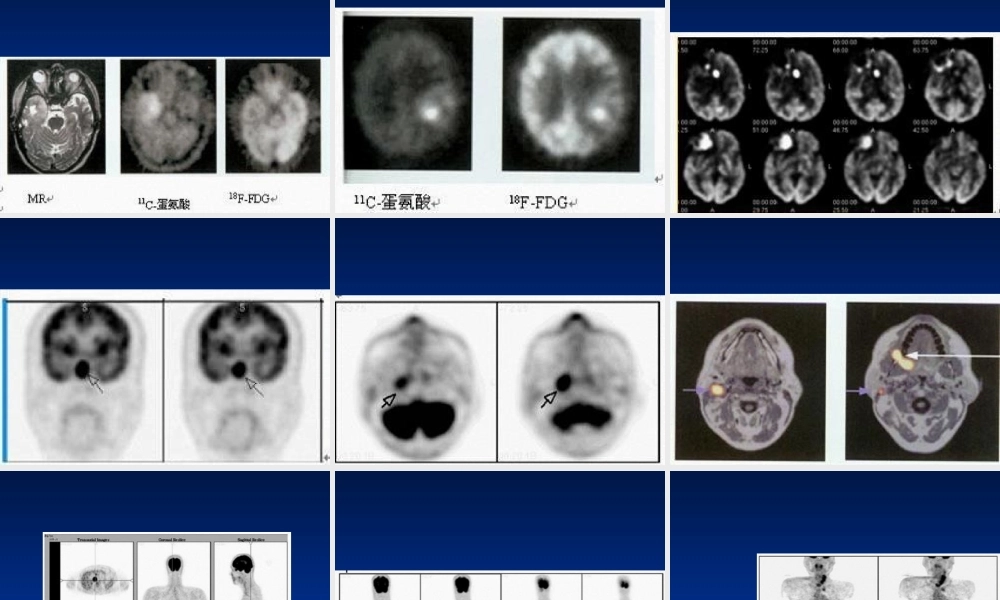

【病史】男,43岁,咳嗽、咳痰半年余,无咯血及体重下降【病史】男,56岁。CT发现颅病例12【病史】男,28岁,头痛、性格改变约半年,MR示右额叶T2信号增高。病例15(fànɡliáo)后1年。病例40【病史】女,58岁。CT查体发现(fāxiàn)胰体尾部占位性病变,大小约10cm。无特殊临床症状。病例43SUV为5.5。病例52【病史(bìnɡshǐ)】男,56岁。腰痛2月,CT、MR示腰4椎体骨质破坏,行手术部分切除,病理为转移性腺癌。胸、腹部及盆腔CT及前列腺B超皆未找到原发灶。(chūxiàn)